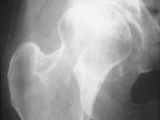

SCFE-Hips

SCFE-Hips